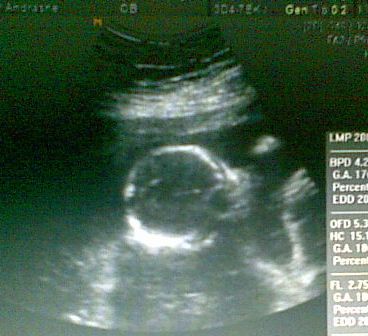

Ja csuklás.Mintha én is éreztem volna,már ...Nem olyan rég figyeltem fel rá,(pár napja),hogy ütemesen rezeg a hasam